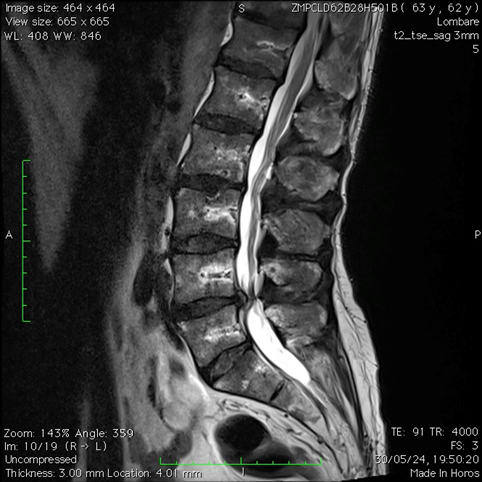

DIAGNOSI:

SPONDILOLISTESI LOMBARE DI II GRADO L5-S1

Risonanza magnetica pre-operatoria

Intervento chirurgico eseguito:

STABILIZZAZIONE PERCUTANEA SEMPLICE

Radiografia lombare post operatoria